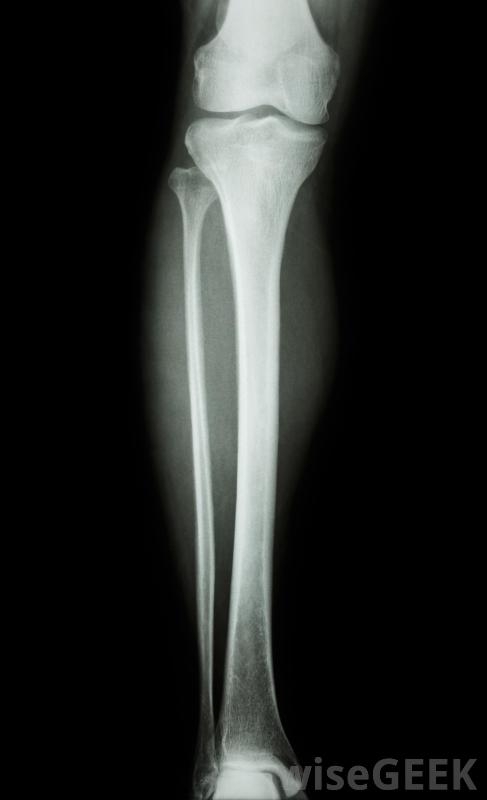

股骨是人体内最难折断的骨头。